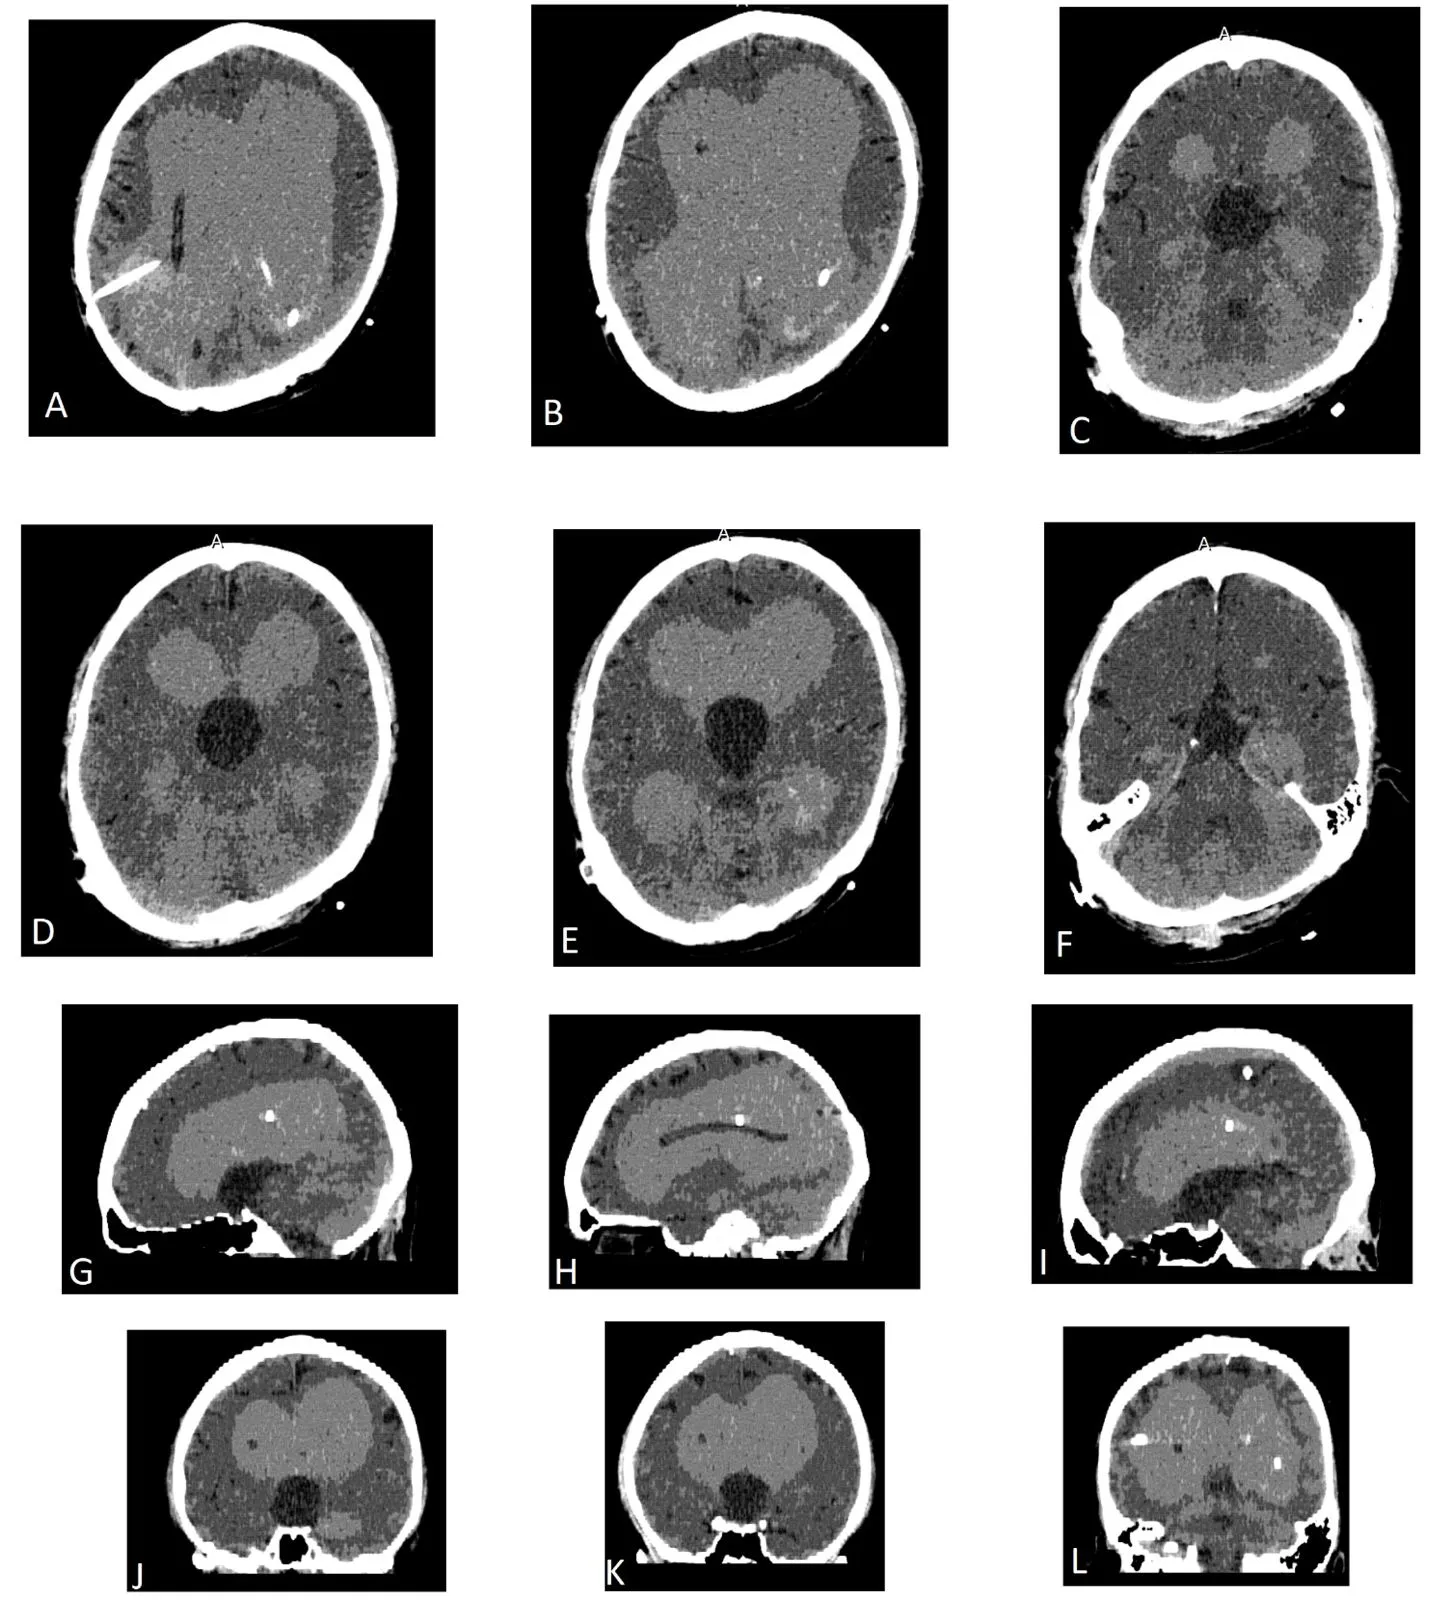

Manjila determined that Dew-Sprague had multiple benign lesions in her brain, but the headaches were centralized in the left cerebral hemisphere, just above her receptive speech area.